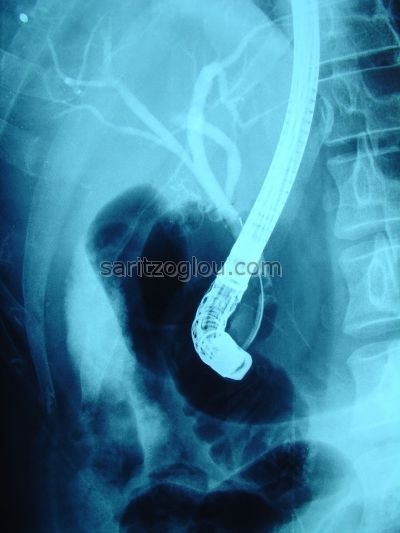

Απεικονίζεται ο καθετήρας μπαλόνι με φουσκωμένο το τελικό του άκρο και κάτω από αυτόν μικρός λίθος στο τελικό άκρο του χοληδόχου πόρου

Απεικονίζεται, καθετήρας τύπου μπαλόνι με φουσκωμένο το άκρο του, καθώς εξέρχεται από τον χοληδόχο πόρο για την αφαίρεση μικρού λίθου, από το τελικό του άκρο.